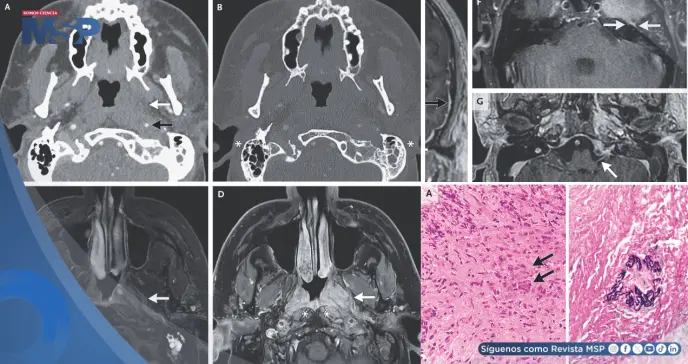

Las imágenes por resonancia magnética y tomografía computarizada mostraron una masa de tejido inflamado en la nasofaringe (la parte superior de la garganta, detrás de la nariz). Esta masa se extendía, afectando los músculos del cuello, la arteria carótida y, de manera crítica, múltiples nervios craneales, incluido el nervio facial.

La ausencia de erosión ósea ayudó a descartar un cáncer primario agresivo.

El diagnóstico llegó con una biopsia de la masa nasofaríngea. El análisis histopatológico del tejido reveló la presencia de inflamación granulomatosa y vasculitis, que es una inflamación y daño directo a las paredes de los vasos sanguíneos.

Este hallazgo tisular se correlacionó con los análisis de sangre, que fueron positivos para un tipo específico de anticuerpo llamado PR3-ANCA. La combinación de estos hallazgos, la afectación de vías respiratorias superiores, la inflamación de vasos sanguíneos y los anticuerpos específicos, confirmó el diagnóstico de Granulomatosis con Poliangeítis (GPA).